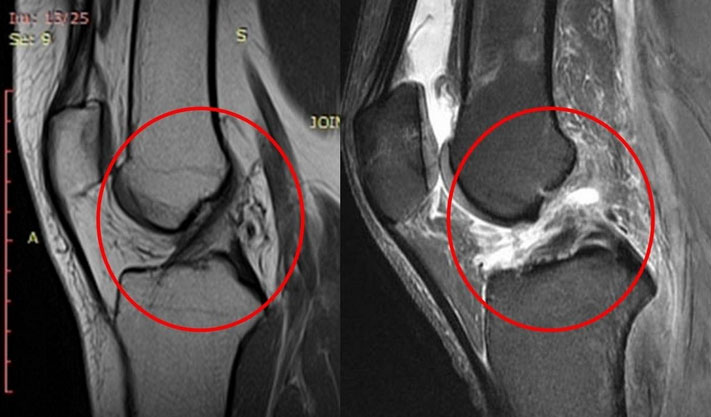

Анализы и диагностика

Первоначальная диагностика разрыва связок начинается с внешнего осмотра, пальпации, а также определения наличия или степени нестабильности сустава (проводятся тесты на стабильность). Также важно оценить сохранность функции сустава и амплитуду движений. Для установления окончательного диагноза применяются инструментальные методы исследования, такие как рентгенография, компьютерная томография (КТ) или магнитно-резонансная томография (МРТ) сустава, а также артроскопия.

Разрыв связок коленного сустава

Связочный аппарат коленного сустава, который представляет собой сложный блоковидно-вращательный механизм, включает в себя внутрисуставные переднюю и заднюю крестообразные связки, а также внутреннюю и наружную боковые связки. Стабильность колена во время движений в основном обеспечивается передней и задней крестообразными связками. Повреждение хотя бы одной из этих связок приводит к нестабильности сустава и увеличивает риск повреждения хряща.

Разрывы крестообразных связок могут быть как частичными, так и полными. В некоторых случаях наблюдается отрыв связки от места её крепления к кости с фрагментом кости — это явление называется переломом Сегонда.

Наиболее распространённым является разрыв крестообразной связки колена, особенно передней, которая повреждается в 15-30 раз чаще, чем задняя. Это связано с тем, что для разрыва задней крестообразной связки требуется значительно большее усилие. В результате, разрывы задней связки фиксируются лишь в 7-10% случаев. Часто наблюдаются одновременные повреждения нескольких связок коленного сустава, и наиболее распространённым является субтотальный разрыв, который представляет собой частичное повреждение передней крестообразной связки.